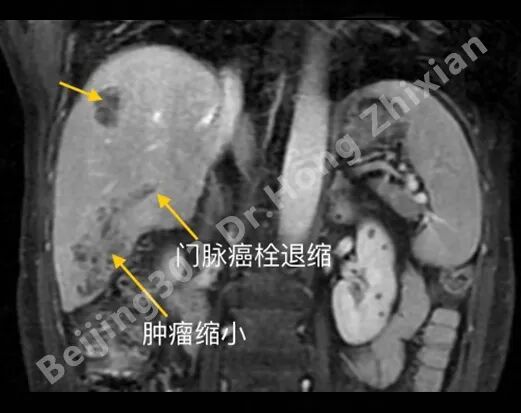

临床随笔丨肝癌术前新辅助治疗:“更优选择”还是“过度治疗”?

病例简介